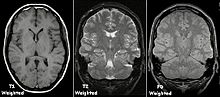

Für eine

-Wichtung

braucht man umgekehrt kurze TE und kurze TR, dann überwiegen die unterschiedlichen Spin-Gitter-Relaxationen verschiedener Gewebe im Bildkontrast. Eine Sequenz mit kurzer TE und langer TR erzeugt einen Kontrast, der sich nur nach der Konzentration der Protonen im Gewebe richtet, die praktisch der Anzahl der Wasserstoffatome entspricht. Diese sogenannten Proton density (PD)-gewichteten Aufnahmen haben einen flauen Kontrast, aber eine hohe Ortsauflösung. Es gibt zahlreiche Weiterentwicklungen dieser einfachen Spinecho-Sequenzen, etwa zur Beschleunigung, oder mit Unterdrückung des Fettgewebesignals. Eine klinische MRT-Untersuchung umfasst unterschiedlich gewichtete Bildserien und mehrere räumlichen Ebenen.

Je nach Gewichtung kommen die verschiedenen Gewebe in charakteristischer Intensitätsverteilung zur Darstellung:

- In der T1-Gewichtung erscheint Fettgewebe hyperintens (signalreich, hell) und damit auch fetthaltige/-reiche Gewebe (z. B. Knochenmark). Diese Gewichtung eignet sich daher gut zur anatomischen Darstellung von Organstrukturen und insbesondere nach Kontrastmittelgabe (Gadolinium) zur besseren Abgrenzbarkeit unbekannter Strukturen (z. B. Tumor).

- In der T2-Gewichtung erscheinen stationäre Flüssigkeiten hyperintens, so dass flüssigkeitsgefüllte Strukturen (z. B. Liquorräume) signalreich und damit hell erscheinen. Dadurch eignet sich diese Gewichtung zur Darstellung von Ergussbildungen und Ödemen sowie z. B. zur Abgrenzung von Zysten gegenüber soliden Tumoren. Bei Röntgenbildern, insbesondere bei der speziellen Röntgentechnik der Computertomographie (CT), werden im Gegensatz dazu die Begriffe hyperdens und hypodens zur Beschreibung des relativen Schwärzungsgrads benutzt.

- Protonengewichtete Bilder sind flau, aber scharf. Knorpel kann sehr detailliert beurteilt werden. In Verbindung mit einem Fettsättigungsimpuls gehören PD-Bilder deshalb zum Standard in Gelenkuntersuchungen.